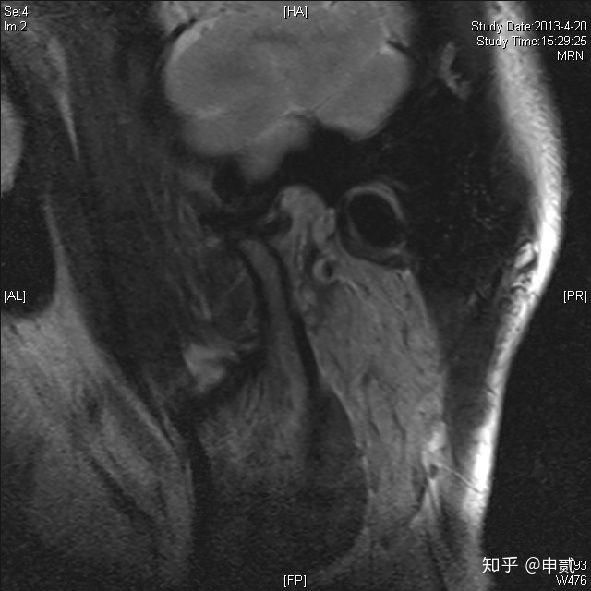

治疗前的MRI检查可见闭口位和张口位,右侧颞下颌关节盘均位于髁突的前方,关节盘扭曲。放射学诊断为:右侧TMJ不可复性关节盘移位伴关节腔积液。

治疗结束后2个月,复查MRI。片中,可以看到闭口位,右侧TMJ关节盘后带位于髁突顶部,张口位时关节盘中间带位于髁突顶部。放射学诊断:双侧TMJ盘髁关系未见异常,此时关节腔积液消失。

正常盘髁关系MRI下表现

闭口位

张口位

可复性盘前移MRI表现

闭口位:关节盘前移

张口位:关节盘回到在髁突顶部

不可复性盘前移

闭口位,张口位关节盘均在髁突前边